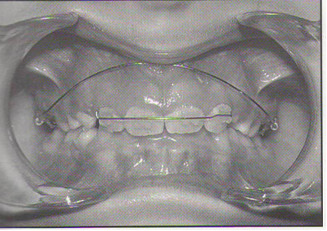

Określ kierunek siły i momentu siły działających na zęby sieczne w sytuacji przedstawionej na rysunku, gdy łuk ciągły z zagięciami tip-back zostanie dowiązany centralnie do łuku fragmentarycznego łączącego górne zęby sieczne:

W sytuacji przedstawionej na rysunku: